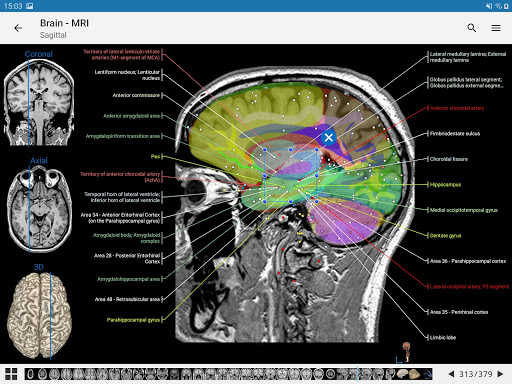

- وحدتان جديدتان: الدماغ - TOF والأوعية الدموية الدماغية ، أطلس التشريح الوعائي العصبي الطبيعي لشرايين الدماغ على الأوعية الدموية الدماغية. - تم إعادة صياغة الواجهة. - تتوفر علامة تبويب جديدة باسم "QuickLinks" ، ترسل وحدات في أقسام من جسم الإنسان وتسمح لك بالسفر السريع إلى الوحدات التي تبحث عنها. الخلل الصغيرة الثابتة.